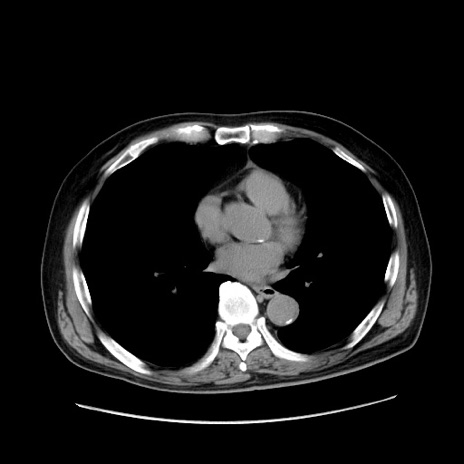

症例30(横断像)

【症例】80歳代男性

【現病歴】約6時間前から臍下部痛が出現。次第に腹部膨隆・背部痛も生じてきたため来院。背部痛の場所は変化しない。

【身体所見】意識清明、BT 36.3℃、BP  131/87mmHg、P 87bpm、SpO2 100%(RA)、臍周囲自発痛・圧痛あり、反跳痛なし、自発痛部位に一致して板状硬あり、腹部膨隆、腸雑音減弱、CVA tenderness両側陰性。